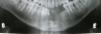

Case reportJ.L.O., a 38-year-old patient was referred to treatment experiencing an extensive lesion involving anterior portion of lower alveolar border with a 10-year progress history. Upon extraoral examination, patient's difficult labial sealing was noticeable by virtue of change in the lower third of the face due to intraoral growth of the lesion. Intraoral clinical evaluation revealed a large-sized lesion involving the anterior portion of the mandible, promoting displacement of teeth 41, 31, 32, 33 and 34 (Fig. 1). Similarly, dental displacement was radiographically clear and the lesion presented slight radiopacity (Fig. 2). Despite the lesion being covered by intact mucosa of normal color, during planning we chose to perform an incisional biopsy prior to definite surgical treatment, by which diagnosis was of inflammatory fibrous hyperplasia. Surgical Access occurred through a wedge incision surrounding the lesion, associated with intrasulcular incision in involved teeth and tissue displacement was performed with the aid of a Molt separator (Fig. 3). Following complete removal of the lesion, dental extraction of involved teeth was performed since they presented compromise of supporting periodontium (Fig. 4). Tissue was repositioned using 5-0 Polypropylene wire and the piece was sent to histopathological examination. Lesion was microscopically described by the presence of dense fibrous connective tissue with multiple vital bone trabeculae, surrounded by uneven pavimentous epithelium (Fig. 5). The presence of mixed inflammatory infiltrate was also seen. In addition to routine HE staining, immunohistochemistry was performed for actin in smooth muscle tissue, in which positivity to HHF-35 was observed (Fig. 6), thus confirming myofibroblastic characteristic of the lesion. Therefore, the diagnosis of excisional biopsy was peripheral ossifying fibroma. The patient recovered with no incidents and clinical and radiographic 12-month follow-up revealed absence of relapses (Figs. 7 and 8).

Upon radiographic evaluation, in some cases the presence of radiopaque diffuse calcifications is observed in a shadow of soft tissues and rarely there is associated bone destruction.4,9 Regarding radiographic appearance of tooth migration, it is present only in 5% of the cases, thus constituting a very rare finding, as well as radicular resorption.1 In this work, marked dental displacement associated with slight radiopacity of the lesion was radiographically observed; however radicular resorption was not seen.